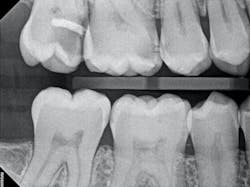

In the case below, tooth No. 2 was diagnosed with symptomatic irreversible pulpitis and symptomatic apical periodontitis with a mesial marginal ridge fracture due to extensive caries (figure 1). Root canal therapy and a full coverage crown were recommended and the patient accepted.

The iTero scanner was able to clearly define the delineation between the soft and hard tissue as can be seen in this image of the digital die trim (figure 3). Radiographs were captured on delivery revealing a clinically acceptable outcome for the patient (figure 4). Direct restorations were completed on teeth Nos. 3 and 4 during this visit.